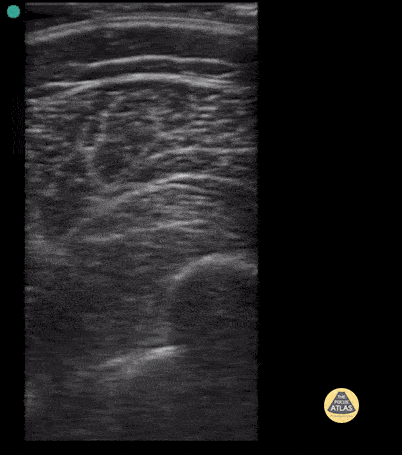

Peds-MSK - Femur Fracture- Case Series, Short Axis

Short axis view of 9 year old male with spiral femur fracture with displacement. Note cortical disruption seen at about 5-6 cm in both long and short axis. Case series 1 of 2 Contributor: Antonio Riera, MD